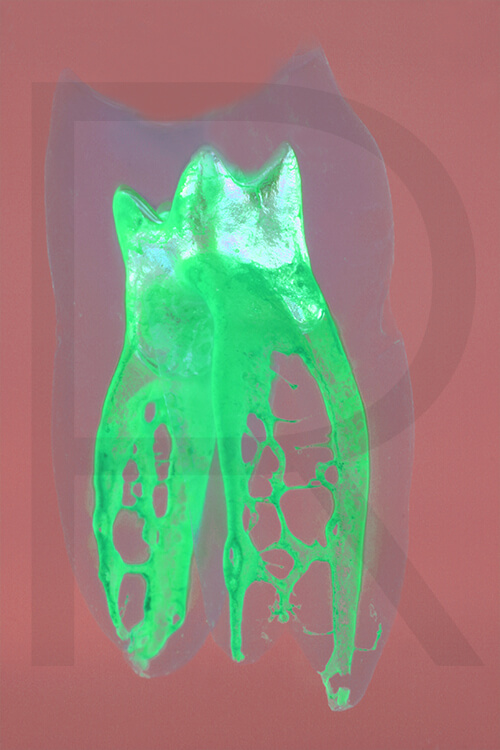

Bildauswahl mit schwebender Aufhängung

Sie haben hier die Möglichkeit, besondere Arbeiten

(© Dr. Holm Reuver) für Ihre Praxis zu erwerben.

Bitte wählen Sie aus klassischen Varianten, Pop Art, Collagen oder Mehrfach-Varianten.

- Foto hinter 3mm Acrylglas, rahmenlos

- hochwertige, unsichtbare Aufhängung, "schwebend“

- Hoher UV-Schutz für lang anhaltend strahlende Farben

- Bruchsicher und leichter als Glas

- Beeindruckende Farben und brilliante Tiefenwirkung

- Druck erfolgt ohne Wasserzeichen

- Bildgröße: 90 x 60 cm, Hochformat

-

Preis: 490,00 Eurozuzüglich 16,90 Euro Versand & Porto innerhalb Deutschlands, weiterer Versand auf Anfrage

Wenn Sie Interesse an den Fotos transparenter Zahnpräparate haben, bieten wir hier die Möglichkeit einige Versionen als Acrylbilder (alle Detailinformationen zu Größe und Preis siehe obige Auswahl) zu bestellen.

Die Bilder sind nicht nur zur Praxisverschönerung geeignet sondern auch eine wertvolle Unterstützung bei der Patientenberatung vor endodontischen Behandlungen.